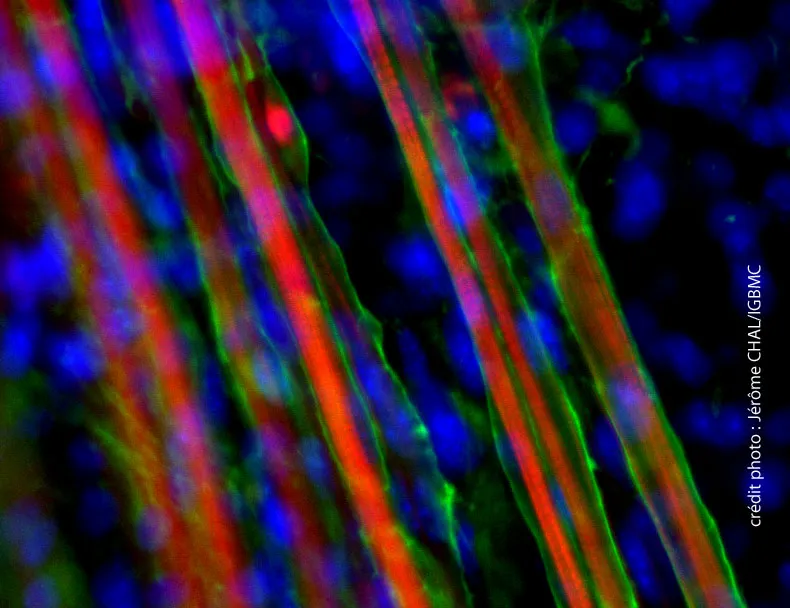

L’étude des deux formes de la protéine DNAJB6 montre que c’est la forme DNAJB6b qui, en désorganisant la structure des fibres musculaires, est responsable de la LGMD1D.